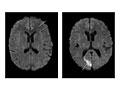

La resonancia magnética es una prueba que utiliza un campo magnético e impulsos de energía de ondas de radio para tomar imágenes de la cabeza. En muchos casos, la resonancia magnética proporciona información que no puede verse en una radiografía, una ecografía ni una tomografía computarizada.

Para una resonancia magnética de la cabeza, usted se tumba con la cabeza dentro de una máquina especial (escáner) que tiene un potente imán. La resonancia magnética puede mostrar daños en los tejidos o enfermedades, como infecciones o inflamaciones, o bien un tumor, un ataque cerebral o convulsiones. La información de una resonancia magnética puede guardarse y almacenarse en una computadora para estudiarla más a fondo. También pueden hacerse fotografías o placas de determinadas vistas.

En algunos casos, puede utilizarse un tinte (material de contraste) durante la resonancia magnética para mostrar imágenes de las estructuras con mayor claridad. El tinte puede ayudar a mostrar la irrigación sanguínea, detectar algunos tipos de tumores y mostrar zonas de inflamación.